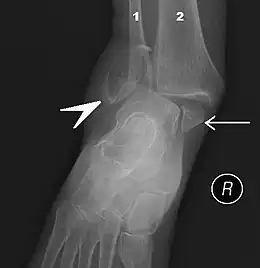

Les ligaments de la partie interne de la cheville.

La cheville est le segment du membre inférieur qui relie la jambe et le pied.

En anatomie, on la nomme région talo-crurale et elle contient l'articulation talo-crurale.